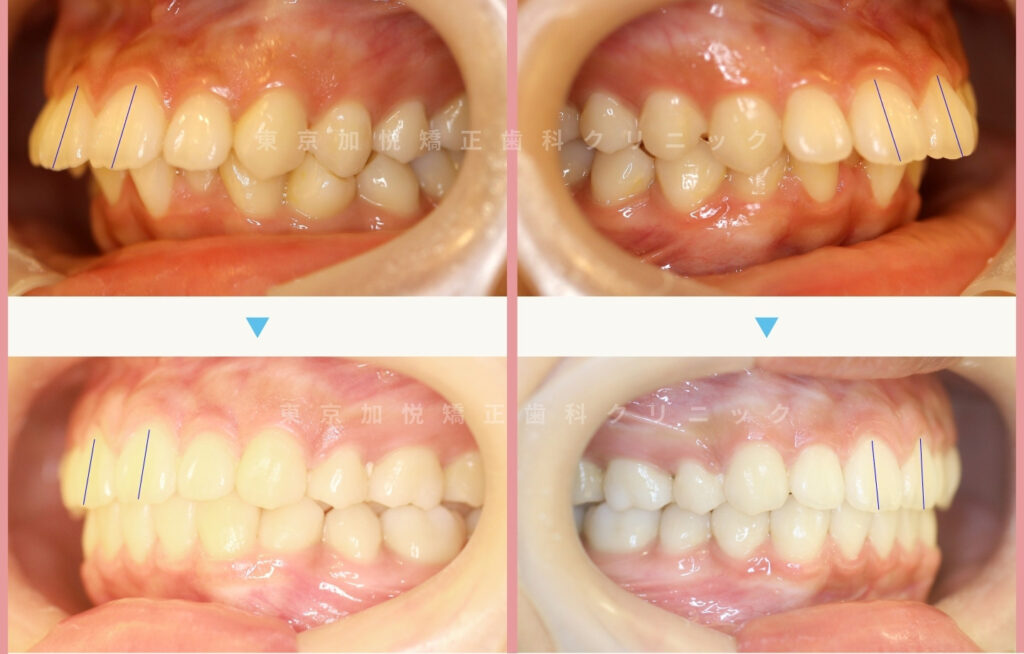

以下は、それぞれの治療前後写真です。

上の前歯の角度の傾きがとれ、前突が改善されました。